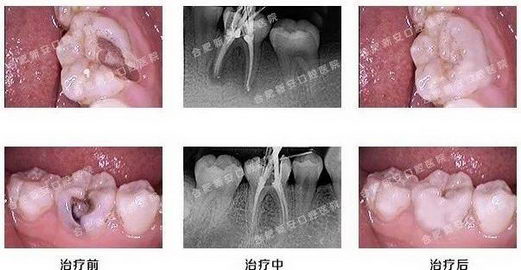

龋齿,就是我们常说的虫牙、蛀牙,是细菌性疾病,因此会引发牙髓炎和根尖周炎,甚至能引起牙槽骨和颌骨炎症。

未经治疗的龋洞是不会自行愈合的,其发展的最终结果是,整颗牙齿丧失。新安口腔会根据孩子的龋齿的数量、疗位、龋病的病变程度,制定最佳的补牙修复方案。